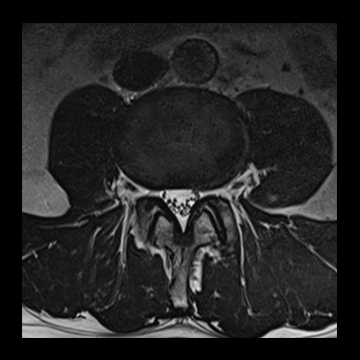

頚椎

T1 TSE, 384 matrix,

T2 TSE, 384 matrix,